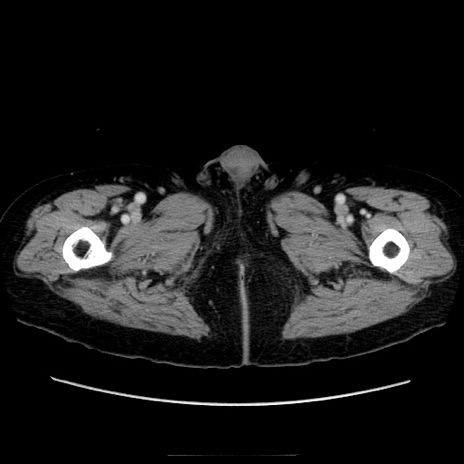

症例21(横断像)

【症例】70歳代男性

【主訴】腹痛

【現病歴】肝硬変・肝細胞癌にてかかりつけの方。約9時間前に食後より腹痛出現。症状が徐々に増悪し、嘔吐出現したため来院。

【既往歴】肝硬変、肝細胞癌(RFA、TACE後)

【身体所見】意識清明、表情苦悶様、BT 36℃、BP 129/78mmHg、P 88bpm、SpO2 97%(RA)、右上腹部から心窩部にかけて圧痛あり、反跳痛なし、筋性防御あり。

【データ】WBC 5800、CRP 0.16